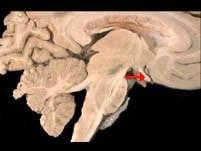

如图箭头所示为视觉系统哪个部位 ( )A、视乳头B、视神经C、视交叉D、视放射E、视束一、单项选择题

问题 如图箭头所示为视觉系统哪个部位 ( )

选项 A、视乳头 B、视神经 C、视交叉 D、视放射 E、视束 一、单项选择题

答案 C